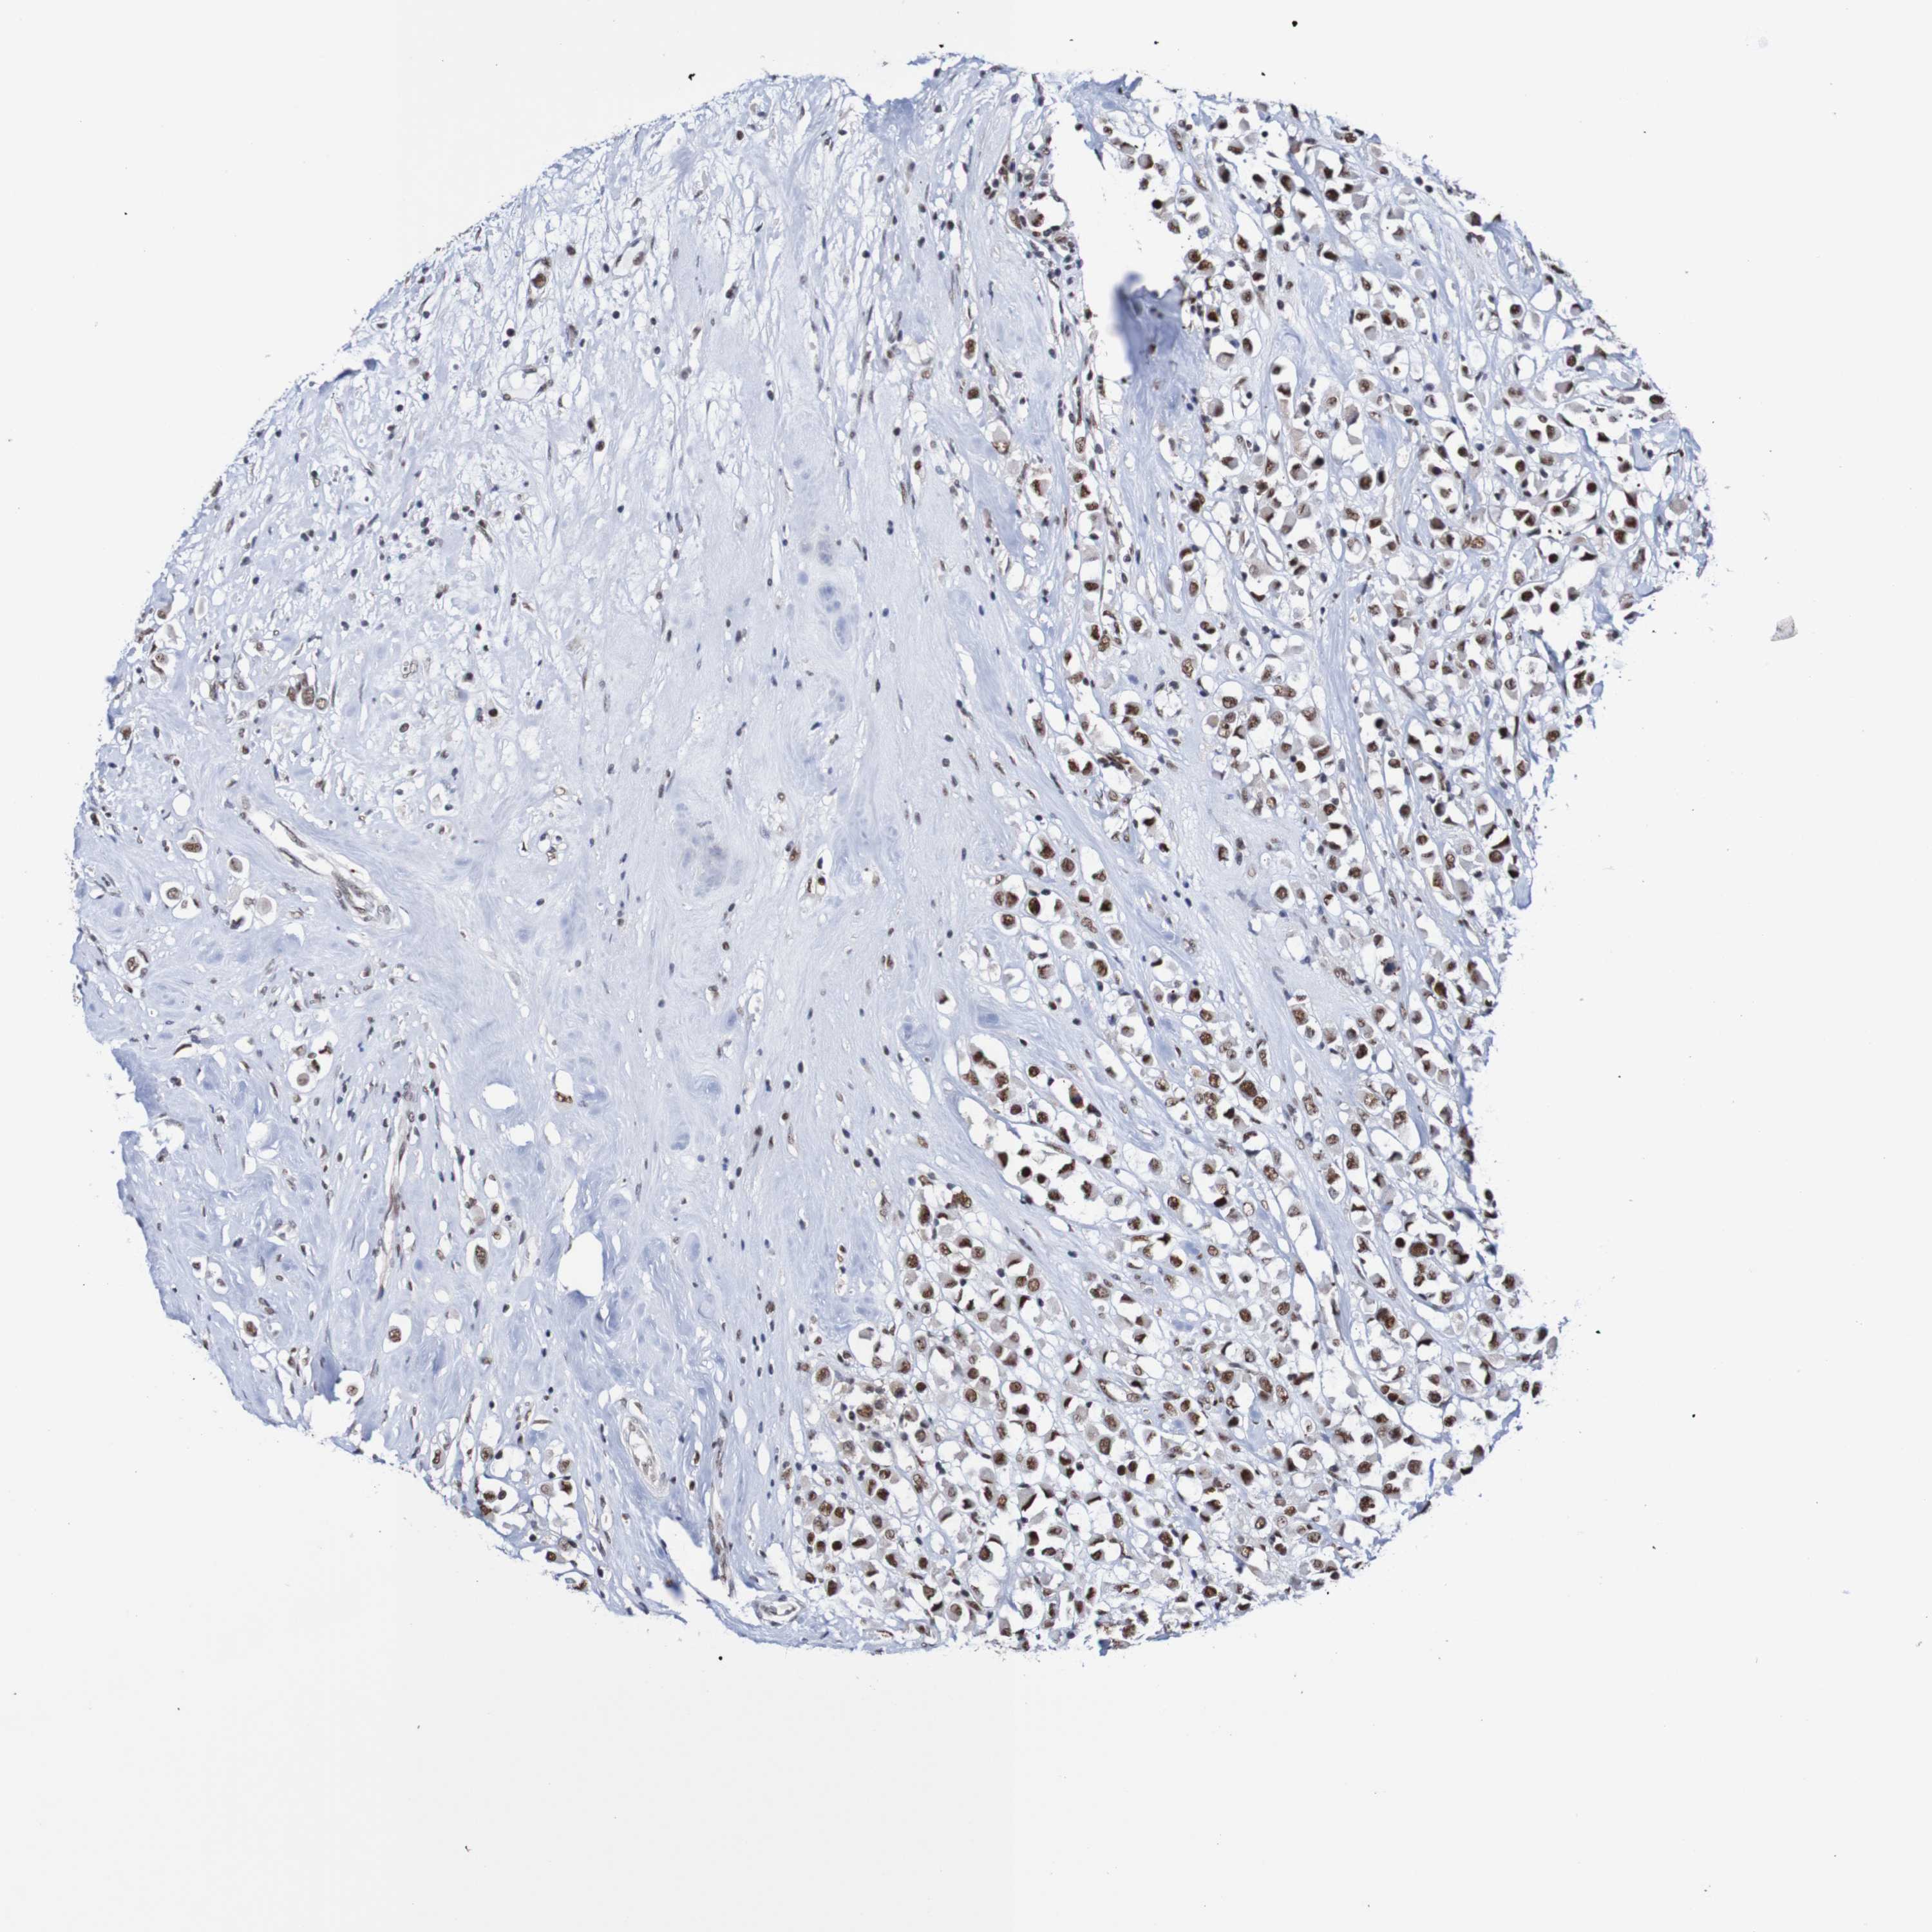

CANCER BREAST CANCER Show tissue menu

BRCA TCGA BRCA VALIDATION PROTEIN EXPRESSION